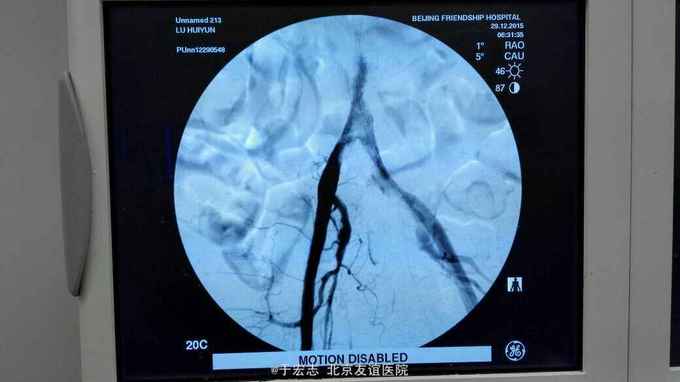

男性76岁,腹主动脉骑跨栓塞,经外院ct证实,病程3天,转至我院。

查体,双下肢大片皮肤青紫,双小腿无感觉,双股动脉波动消失

全腔内技术操作,用8F rotarex机械取栓导管操作,术前留置股静脉鞘,边操作边放静脉血,减少毒素吸收。静脉血经自体血回收处理。 操作完成后以血管缝合器缝合股动脉穿刺点,加压包扎。 患者转重症医学科途中出现心跳骤停,于手术室心外按压2小时复苏成功,转重症医学科血滤治疗。术后五小时生命体征均可维持,但家属还是放弃进一步治疗转运回当地治疗。